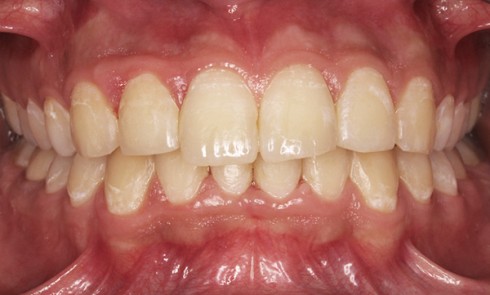

Article réservé à nos abonnés Choix d’une approche additive dans les traitements d’usures érosives et attritives : intérêts des full mock up

Les patients atteints d’érosion/usure de nature chimique consultent de manière quasi exponentielle au sein des cabinets, avec des degrés d’atteinte...